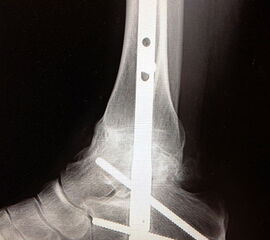

Erreichen eines schmerzfreien oberen Sprunggelenkes mit belastbarem und plantigrad aufsetzbarem Fuss (Abb. 1a und b) unter Verzicht auf die Bewegungsfunktion des oberen Sprunggelenkes. Operative Resektion der arthrotisch veränderten Gelenkflächen bis in den subchondralen frischen Knochen von Tibia und Talus. Fusion mittels Kompressionsschrauben oder Arthrodeseplatten, bedarfsweise Arthrodesenagel.

Abbildung 1a

Abbildung 1b